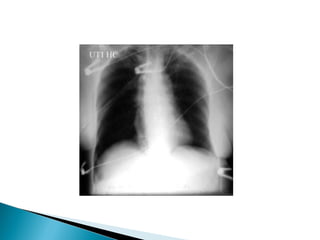

   A radiografia simples do tórax é um dos

exames radiológicos mais utilizados na

prática médica.